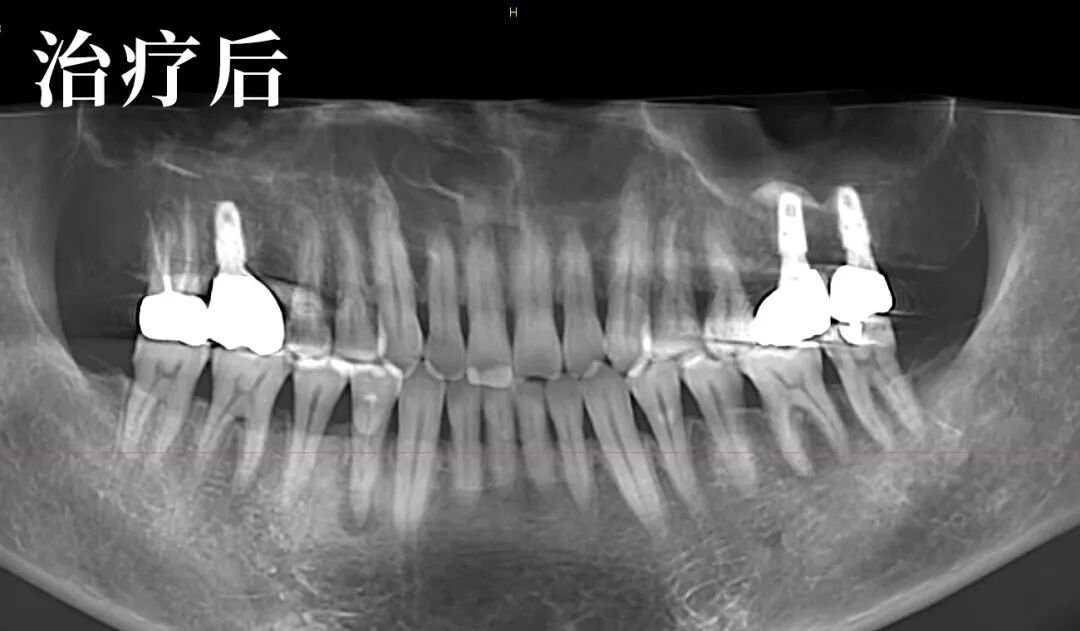

这是一个为李先生量身定制的方案:待软组织充分恢复后,通过重新取模和精细的牙合调整,制作能适应其独特关节结构的新修复体。

治疗过程中,朱医生的操作稳健而轻柔。他不仅关注牙齿本身,甚至细致地观察到并引导纠正了患者长期形成的偏侧咀嚼习惯,从根源上巩固了治疗效果。